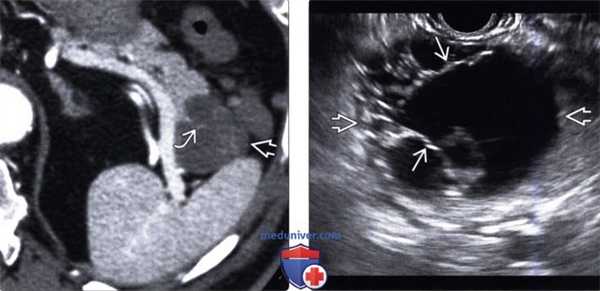

(Левый) При КТ с контрастным усилением на аксиальной томограмме в хвосте поджелудочной железы определяется четко отграниченное округлое кистозное образование с контрастными плохо различимыми внутренними перегородками.

(Правый) При эндоскопическом УЗИ в хвосте поджелудочной железы выявлено четко отграниченное многокамерное кистозное новообразование с внутренними перегородками.